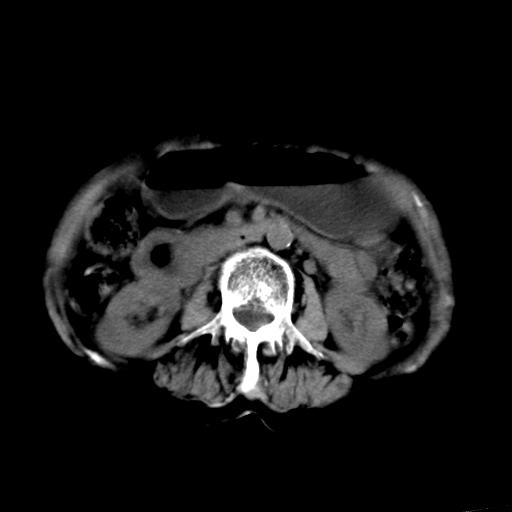

以下是引用杀毒软件在2009-3-4 17:38:00的发言:[br]为何没有喝照影剂呀? 胆总管及肝内胆管扩张,增强吧。[br][br]考虑-----十二指肠占位----建议----十二指肠镜检查[br][br]

以下是引用jiangjing在2009-3-4 17:45:00的发言:[br]低位胆道梗阻。十二指肠降段局部管壁增厚。扫描效果不理想,建议ct增强及ercp。

以下是引用杀毒软件在2009-3-4 17:38:00的发言:[br]为何没有喝照影剂呀? 胆总管及肝内胆管扩张,。增强吧。[br][br]考虑-----十二指肠占位----建议----十二指肠镜检查[br][br][br][br][本贴已被 杀毒软件 于 2009-3-4 17:56:38 修改过]